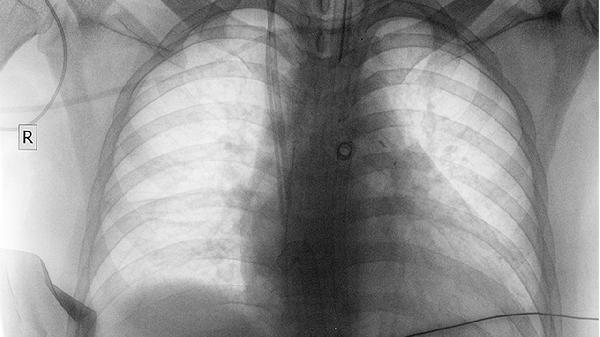

CT检查可见多发圆形结节,多分布于肺外周带,结节边缘光滑或分叶状。部分病例呈现"炮弹样"转移特征,即大小不等的多发性结节。PET-CT能同时显示原发灶与转移灶的代谢活性。